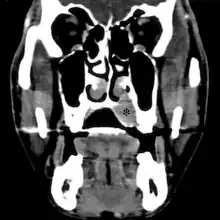

Medical imaging

On conventional radiographs, the most common osseous presentation is a permeative lytic lesion with periosteal reaction.[1] The classic description of lamellated or "onion-skin" type periosteal reaction is often associated with this lesion.[1] In addition, Magnetic resonance imaging (MRI), Computed axial tomography (CT) and PET scan can help fully define the Ewing sarcoma and assess any spread.[1]

MRI will show the full bony and soft tissue extent and relate the tumor to other nearby anatomic structures (e.g. vessels). Gadolinium contrast is not necessary as it does not give additional information over noncontrast studies, though some current researchers argue that dynamic, contrast-enhanced MRI may help determine the amount of necrosis within the tumor, thus help in determining response to treatment prior to surgery. Computed axial tomography (CT) can also be used to define the extraosseous extent of the tumor, especially in the skull, spine, ribs, and pelvis. Both CT and MRI can be used to follow response to radiation and/or chemotherapy. Bone scintigraphy can also be used to follow tumor response to therapy. In the group of malignant small round cell tumors that includes Ewing sarcoma, bone lymphoma, and small cell osteosarcoma, the cortex may appear almost normal radiographically, while permeative growth occurs throughout the Haversian channels. These tumors may be accompanied by a large soft-tissue mass while almost no bone destruction is visible. The radiographs frequently do not shown any signs of cortical destruction. Radiographically, Ewing's sarcoma presents as "moth-eaten" destructive radiolucencies of the medulla and erosion of the cortex with expansion.